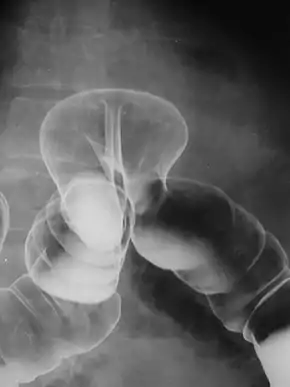

By far the most common hernias (up to 75% of all abdominal hernias) are the so-called inguinal hernias. Inguinal hernias are further divided into the more common indirect inguinal hernia (2/3, depicted here), in which the inguinal canal is entered via a congenital weakness at its entrance (the internal inguinal ring), and the direct inguinal hernia type (1/3), where the hernia contents push through a weak spot in the back wall of the inguinal canal. Inguinal hernias are the most common type of hernia in both men and women. In some selected cases, they may require surgery. There are special cases in which the hernia may contain both direct and indirect hernia simultaneously pantaloon hernia, or, though very rare, may contain simultaneous indirect hernias.[19]

A hiatus hernia is a particular variant of this type, in which the normal passageway through which the esophagus meets the stomach (esophageal hiatus) serves as a functional "defect", allowing part of the stomach to (periodically) "herniate" into the chest. Hiatus hernias may be either "sliding", in which the gastroesophageal junction itself slides through the defect into the chest, or non-sliding (also known as para-esophageal), in which case the junction remains fixed while another portion of the stomach moves up through the defect. Non-sliding or para-esophageal hernias can be dangerous as they may allow the stomach to rotate and obstruct. Repair is usually advised.